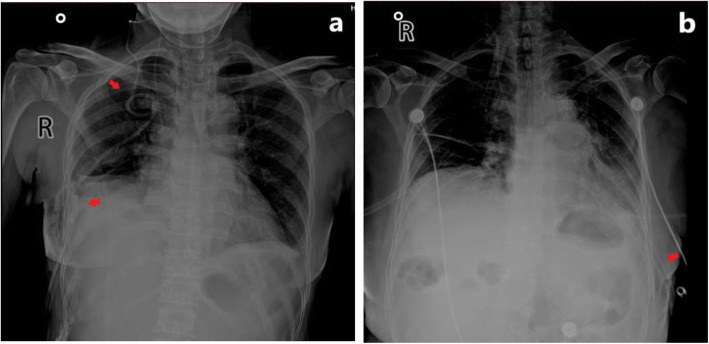

In this study, the drainage days in group A were shorter than those in group B, and the postoperative hospital stay in group A was shorter than those in group B, and the total postoperative drainage volume was also lower than that in group B, showing statistically significant differences. The inner wall of an ultrafine chest drainage tube is smooth, with strong anti-coagulation ability and good flexibility. It can be coiled in the costophrenic angle or followed between the lung and chest wall, making the drainage tube more smooth and sufficient. However, due to thick texture of the 24F chest drainage tube, it is not easy to be completely placed in the costophrenic angle or followed between the chest wall and the lung lobe. Therefore, it might compress the lung lobe and diaphragm muscle, stimulating the production of pleural effusion, thus prolonging the drainage period. See Fig. 3.

Fig. 3.

Postoperative X-ray of the thoracic cavity of patients; a the arrows indicate that two 8F chest drainages tubes are placed in the thoracic cavity; b the arrows indicate that one 24F chest drainage tube is placed in the thoracic cavity